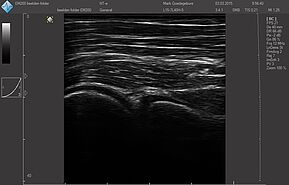

Датчики имеют большую чувствительность и высокое разрешение, благодаря чему обеспечивают максимальное проникновение и улучшают соотношение сигнал /шум. В результате формируется максимально четкая детализированная картинка УЗИ изображения.

- Усовершенствованная технология уменьшения спекл-шумов

- Улучшение изображения